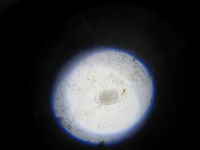

Hackenwurm (Ei)